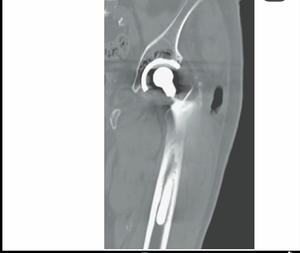

What is most likely underlying diagnosis in this 82 years old patient with diabetes mellitus who had gone total hip replacement 10 years previously ? A. Colon cancer B. Hypogammaglobulinemia C. Osteosarcoma D. Tuberculosis E. Hypophosphatasia

A. Free air extending lateral to the greater trochanter. Intra-articular cultures grew Clostridium septicum, which has a known association with colorectal cancer. Subsequent colonoscopy revealed a fungating colonic adenocarcinoma. It was in USMLE STEP base